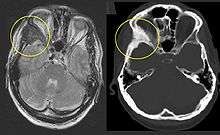

Children with fibrous dysplasia in the appendicular skeleton typically present with limp, pain, and/or pathologic fractures. Frequent fractures and progressive deformity may lead to difficulties with ambulation and impaired mobility. In the craniofacial skeleton, fibrous dysplasia may present as a painless “lump” or facial asymmetry. Expansion of craniofacial lesions may lead to progressive facial deformity. In rare cases patients may develop vision and/or hearing loss due to compromise of the optic nerves and/or auditory canals, which is more common in patients with McCune-Albright syndrome associated growth hormone excess.[7] Fibrous dysplasia commonly involves the spine, and may lead to scoliosis, which in rare instances may be severe.[8] Untreated, progressive scoliosis is one of the few features of fibrous dysplasia that can lead to early fatality.